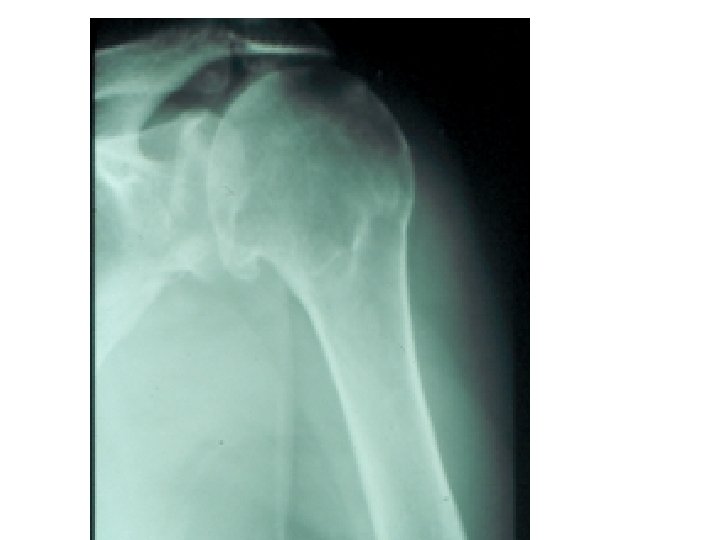

SEMIOLOGIE DE L’EPAULE IV – DIAGNOSTIC ETIOLOGIQUE A – Atteintes périarticulaires B – Rétraction capsulaire de l’épaule (épaule gelée – algodystrophie) C – Arthroses de l’épaule D – Arthrites – rhumatismale (contexte) – infectieuse +++